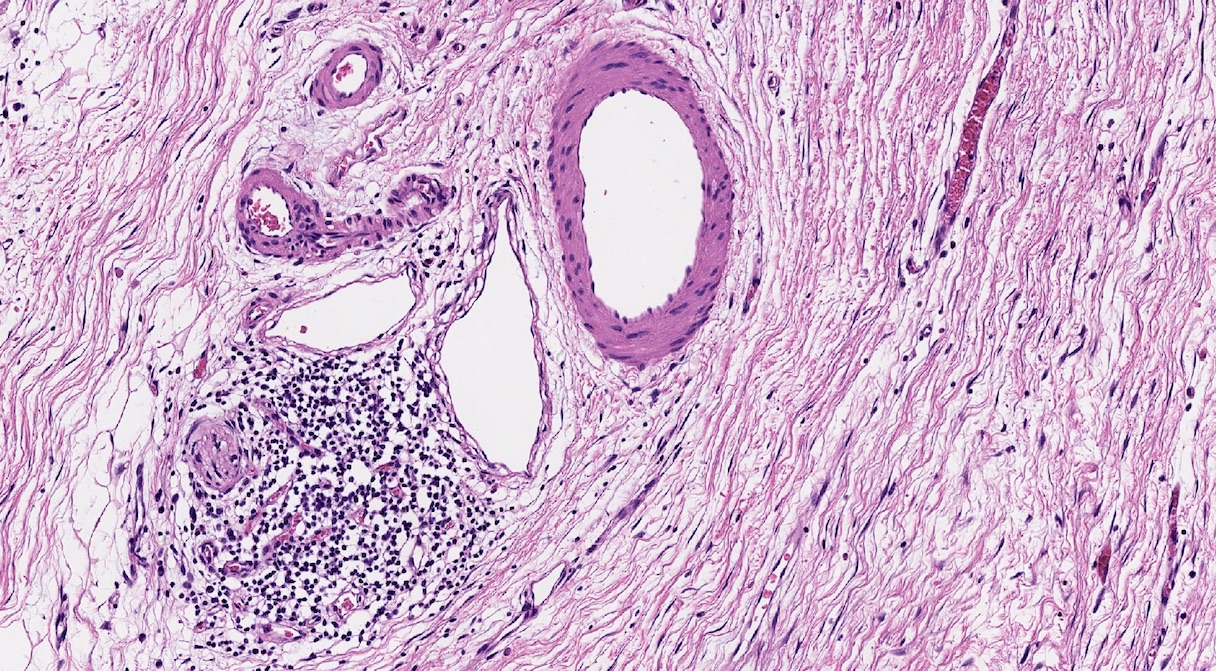

Microscopic (histologic) description

- Triad of cardinal features: fibrosis, loss of acinar tissue, duct changes (Pancreatology 2020;20:586)

- Fibrosis is initially perilobular; during disease progression, it involves the pancreatic lobular units, eventually replacing the acinar parenchyma (so called intralobular fibrosis)

- Ductal changes include distortion of ductal profiles, ectasia, presence of intraluminal concretions of amorphous material (so called protein plugs), squamous metaplasia, intraductal calcification

- Foci of periductal chronic inflammation and fat necrosis represent a common finding

Microscopic (histologic) images